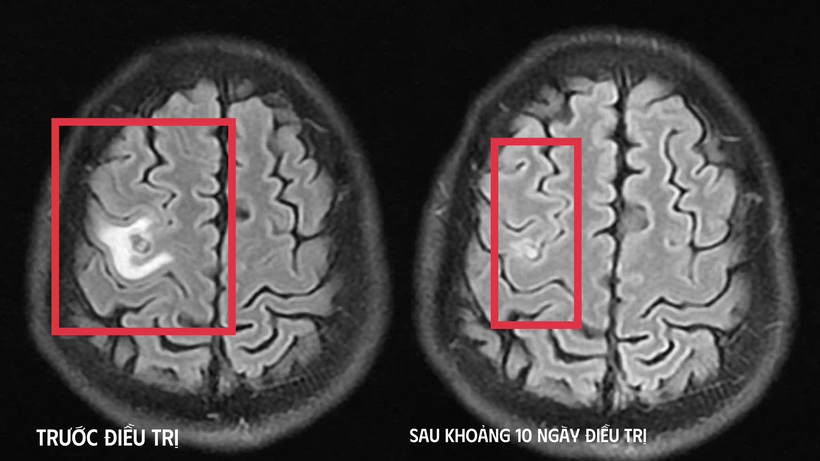

Khi tái khám gần một tháng sau, kết quả chụp cộng hưởng từ cho thấy tổn thương não thu nhỏ ( cụ thể hình dạng nang) rõ rệt, phù não giảm, không còn dấu hiệu tiến triển, đáp ứng điều trị tốt. Bệnh nhân tiếp tục được chỉ định thêm một đợt thuốc củng cố và theo dõi lâu dài.

Hình ảnh sán não làm tổ trong não bệnh nhân (trái) và kết quả sau 10 ngày điều trị